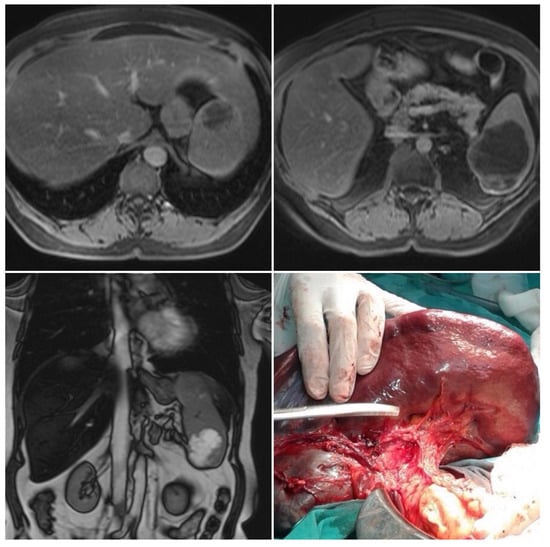

2.5. Imaging Examination

3. Multidisciplinary Expert Consultation and Final Diagnosis

4. Treatment